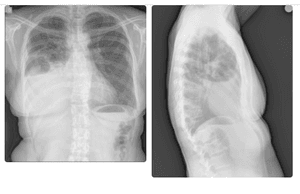

Tive câncer de mama 8 anos atrás, fiz o tratamento e tive a cura, porém precisei fazer uso de uma medicação que pode ter sido a causa de uma osteoporose grave, tornando meus ossos enfraquecidos, o que pode ter sido a causa de algumas costelas quebradas e um achatamento de uma vértebra. Além disso, apareceu nos exames um derrame pleural e será preciso fazer uma cirurgia pra descobrir a causa, que pode ser um retorno do câncer. Hoje me encontro na fila do SUS para fazer a cirurgia, pois estou desempregada e sem plano de saúde.